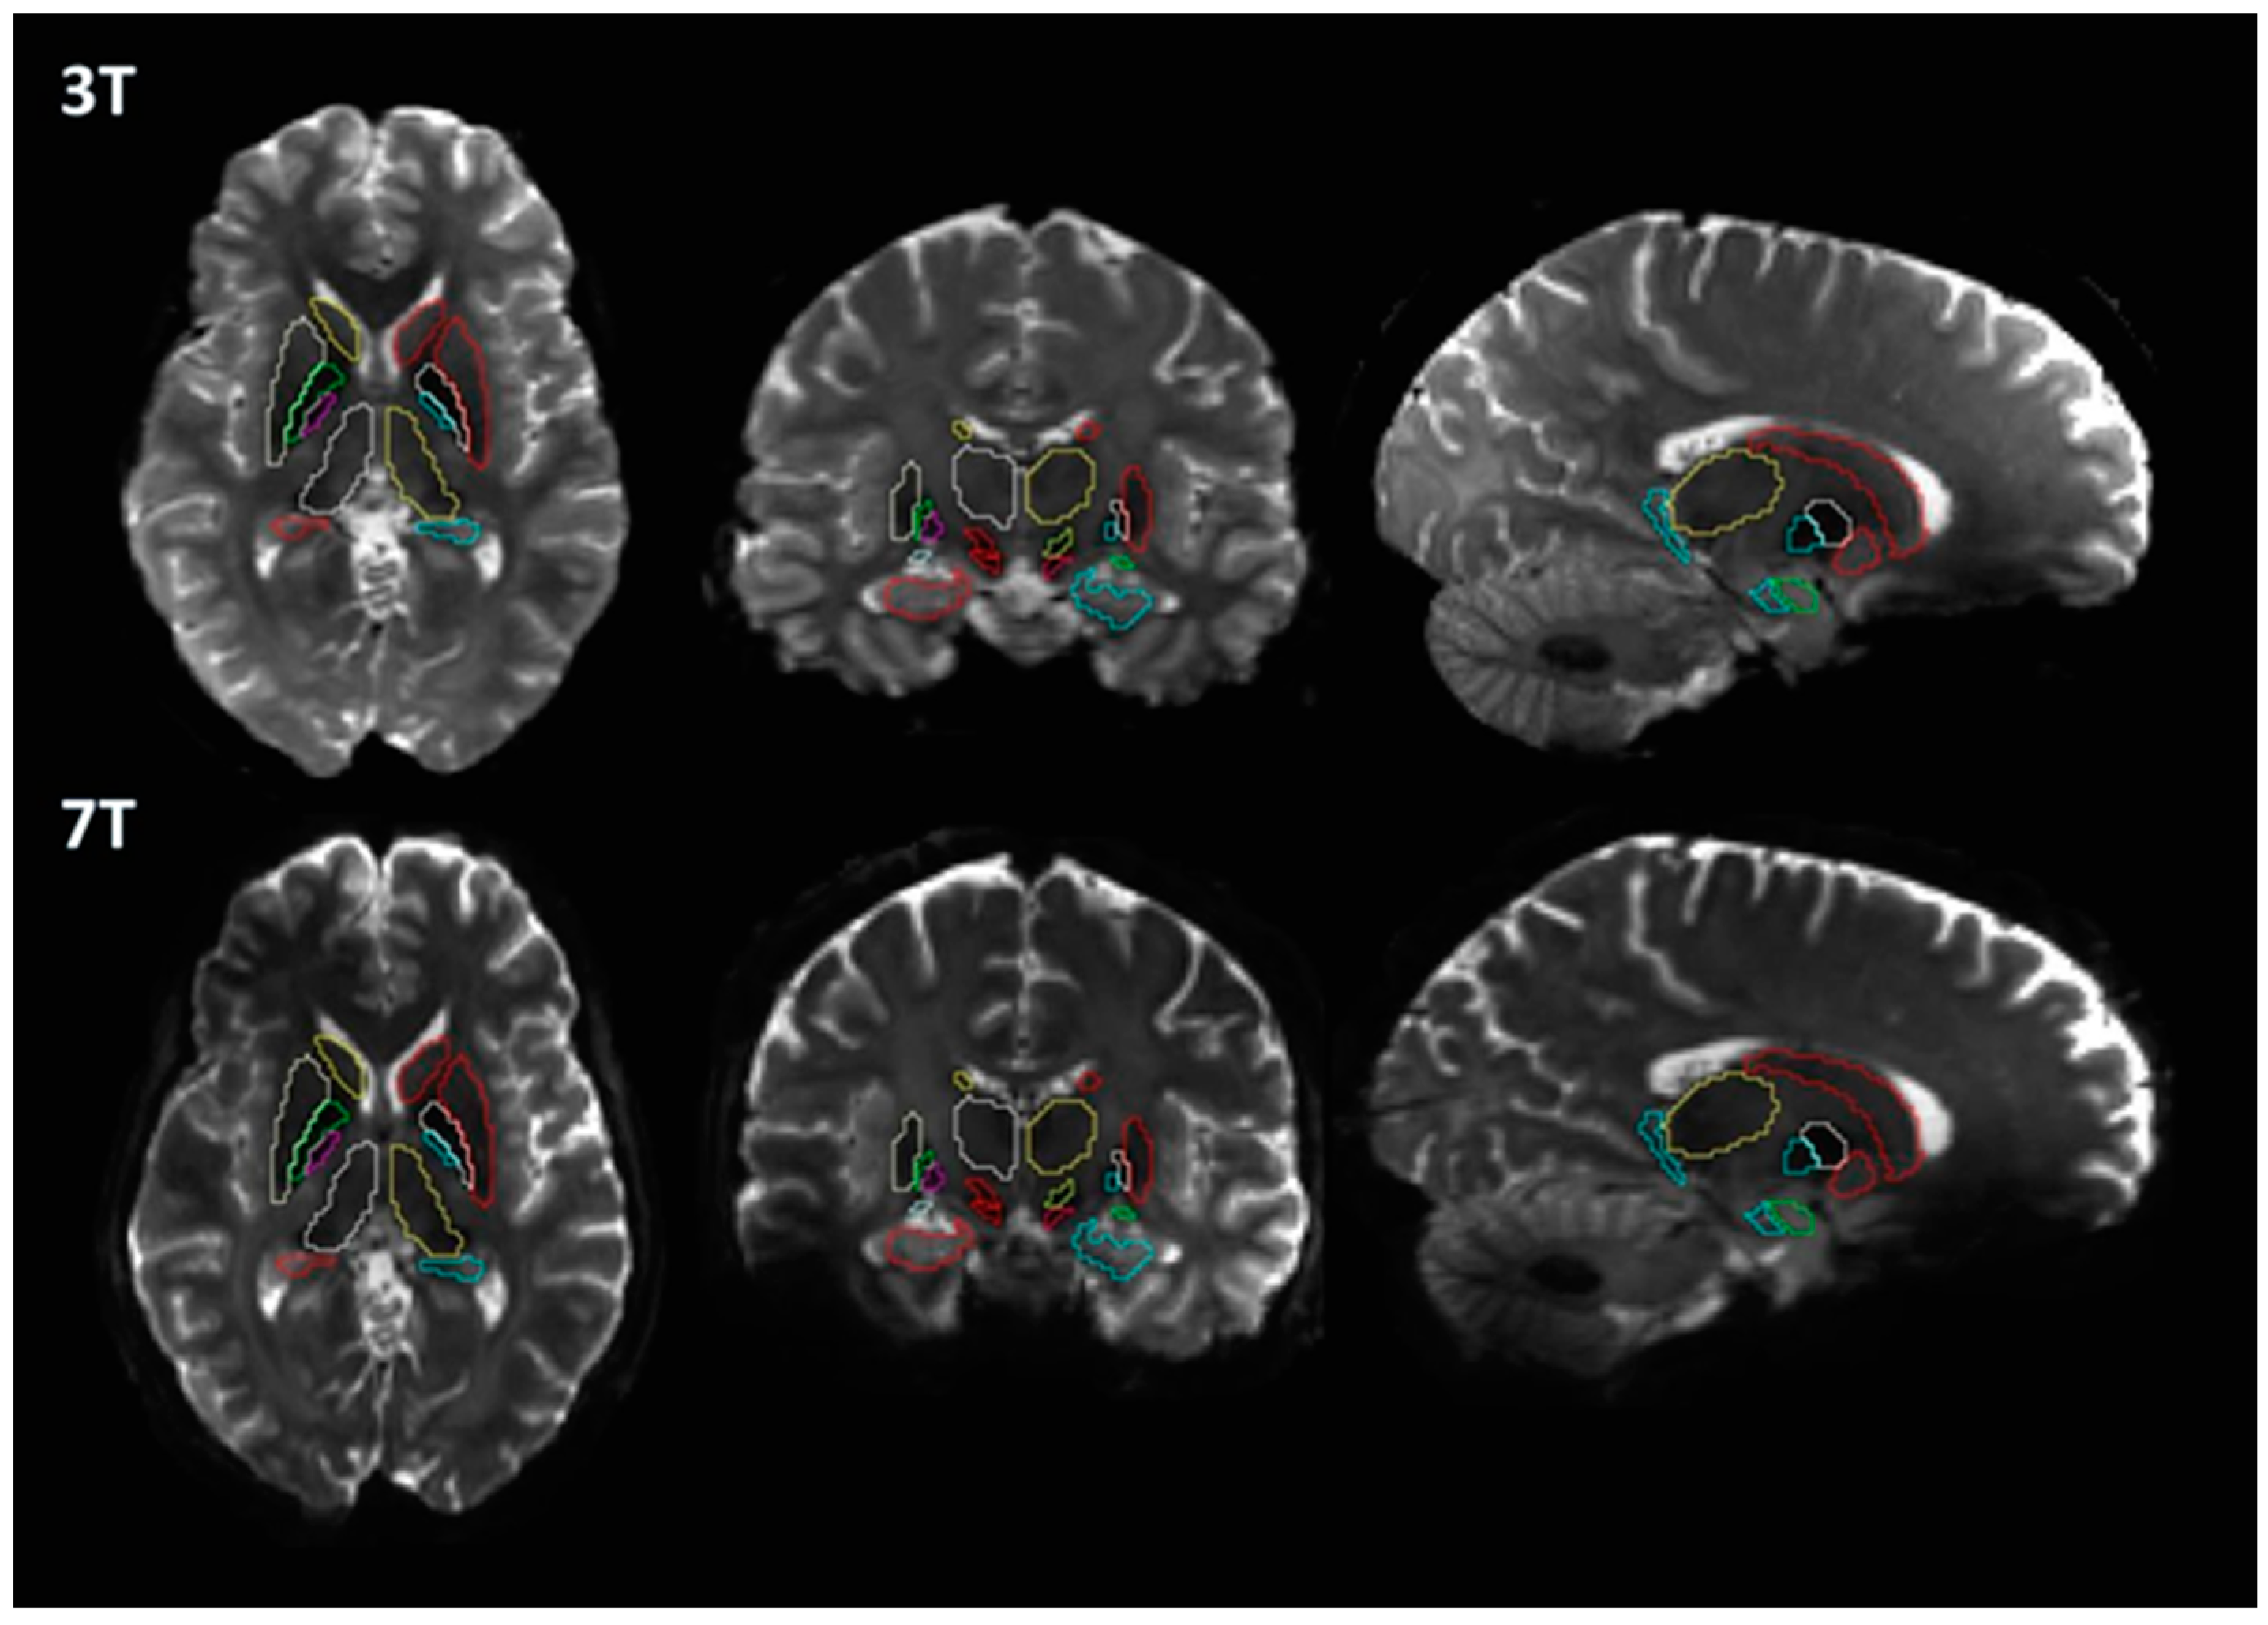

2.2. MRI Acquisition

2.3. Image Processing